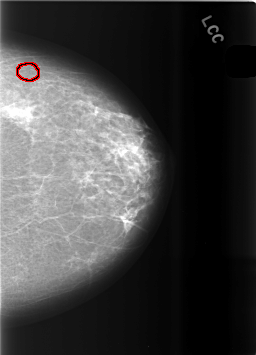

C_0483_1.LEFT_CC

LEFT_CC LINES 5672 PIXELS_PER_LINE 4096 BITS_PER_PIXEL 12 RESOLUTION 50 OVERLAY

FILE: C_0483_1.LEFT_CC.OVERLAY

TOTAL_ABNORMALITIES 1

ABNORMALITY 1

LESION_TYPE CALCIFICATION TYPE PLEOMORPHIC DISTRIBUTION CLUSTERED

ASSESSMENT 4

SUBTLETY 4

PATHOLOGY BENIGN

TOTAL_OUTLINES 1

BOUNDARY